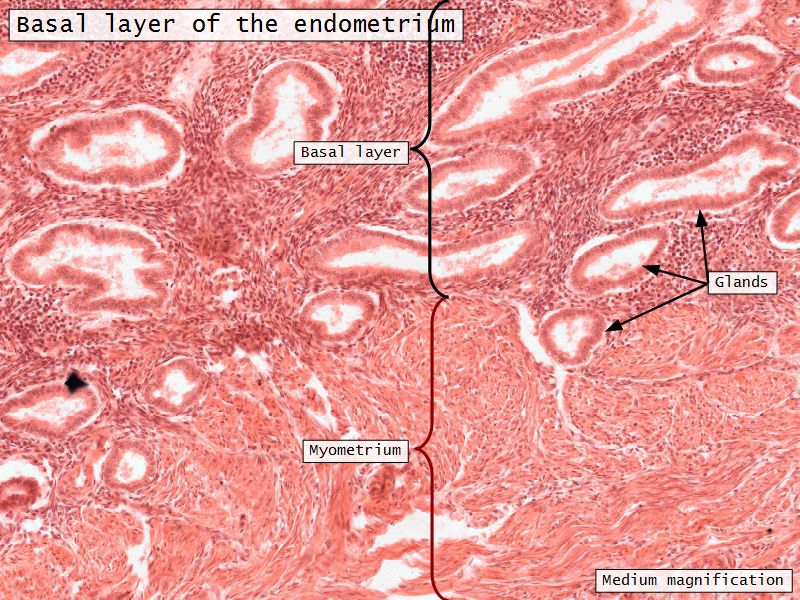

Endometrium

- Formation of placenta

- Hormonally modulated cyclic alterations

- menstrual cycle

- Two layers

- Thick superficial functional

- Deeper basal layer

- Separation indistinct

Endometrium Stroma

- Mesenchymal-like CT

- Reticular fibres

- Stellate-shaped cells

- Macrophages

- Lymphoid elements

- Functional layer

- Basal layer

Basal layer

- Thin deeper layer

- Preserved during menstruation

Endometrial glands

- Extend through basal layer

- Source of cells to reestablish endometrium